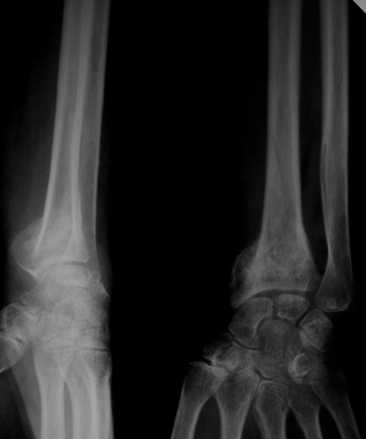

Уважаемые коллеги! Обратилась женщина, 55 лет. Травма 3 месяца назад, лечилась по месту жительства (Рис.1). Косорукость, боли, ограничение движений.

Досняли - рис.2-6. Хотелось-бы услышать мнения об объеме операции. С уважением, Юрий Алексеевич Булахтинглавный травматолог Камчатского Военно-морского госпиталя

u pazientki po nauchnomu ulna abutment/impingment syndrome posle posttraumaticheskogo ukorochenia radiusa

na rengene znachitelnoe ukorochenie radiusa, sustavnaia poverchnost naklonena dorsalno chresmerno , chetko vidno nekongruentnost DRUJ - distalnogo radioulnarnogo sustava ,ulna prosto vtikaetsia v triquetrum .

Да, действительно, в наличии так называемый посттравматический ulnar impaction syndrome. Есть несколько вариантов лечения этой патологии-данного случая. Вполне можно выбрать вариант и предложенной выше тактики. А кто-то даже после остеотомии лучевой кости наложит аппарат внешней фиксации и одновременно устранит дорсальную ангуляцию и удлинит лучевую кость. Можно предусмотреть и другие варианты. Если не очень расстраивает дорсальная ангуляция, то при отсутствии артроза в области дистального радиоульнарного сочленения ( а пока такого, по-видимому, нет)и нестабильности этого сустава можно просто укоротить локтевую кость. Причем возможно сделать поперечную остеотомию ( если есть ладонный или тыльный подвывих головки локтевой кости, то можно сделать еще и клиновидную остеотомию по ладони или по тылу), либо выполнить косую остеотомию ( при подвывихе головки даже клин в этом случае не надо делать). Если есть артроз, нестабильность, то нужно рассматривать другие варианты - Дарраха в модификациях, Сауве-Капанджи, артропластику(?).